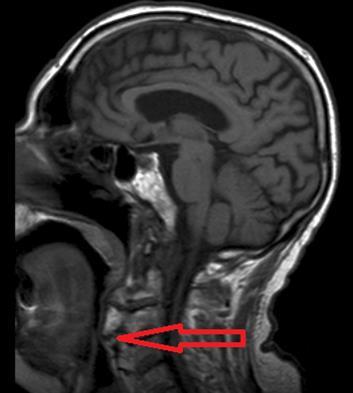

Brain and cervical MRI were performed to exclude recent brain ischemic lesions and to investigate the spinal chord involvement in relation to the known severe osteophytosis. The brain MRI showed only signs of chronic vasculopathy and no images related to acute events. The neck MRI revealed no medullary compression or signal alterations; osteophytes originating from C1 to C7 were described and had a compressive and displacing effect on the upper aero-digestive ways and laryngeal post-cricoid area. Osteophytes were forming bony bridges in the anterior prevertebral space from C3 to C7.

Figure 1.Osteophytes-induced upper airways obstruction